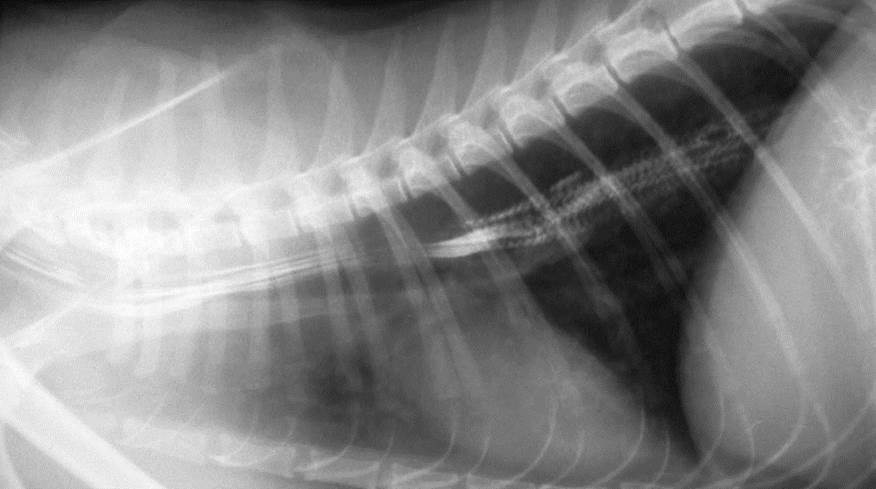

What can be seen here?

Regional megaoesophagus

Vascular ring anomaly

Dilation of oesophagus cranial to this